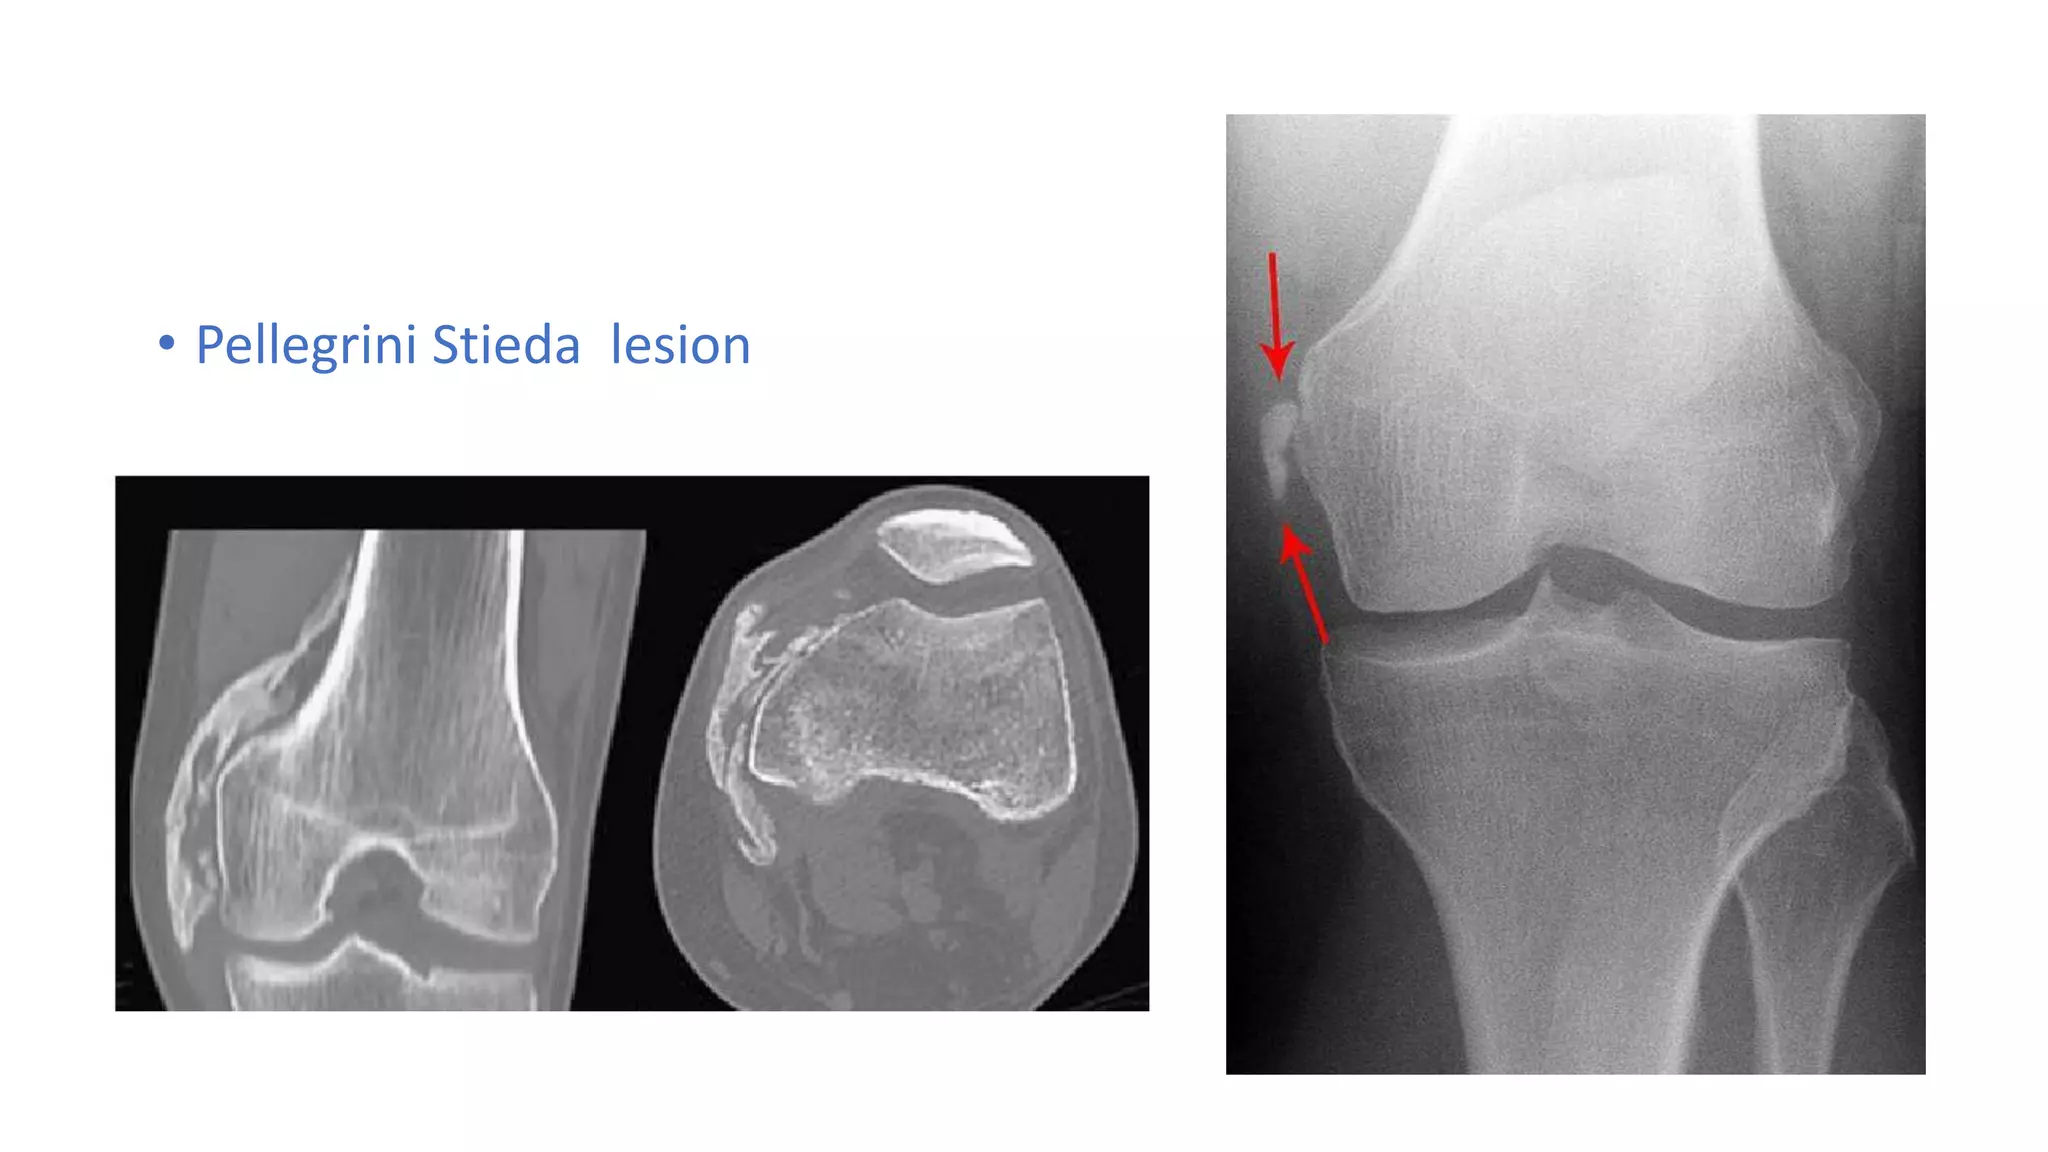

A Pellegrini Stieda Lesion is a rare condition characterized by the calcification of the medial collateral ligament (MCL) of the knee. The MCL is a crucial ligament that provides stability to the inner side of the knee joint. When this ligament becomes calcified, it can lead to pain, stiffness, and reduced range of motion. The condition is named after the Italian surgeon Pellegrini and the German surgeon Stieda, who first described it in the late 19th century.

Diagnosing a Pellegrini Stieda Lesion involves a combination of physical examination, medical history, and imaging tests. The diagnostic process typically includes the following steps:

• Imaging Tests: X-rays, ultrasound, or MRI scans to visualize the calcification and assess the extent of the damage.